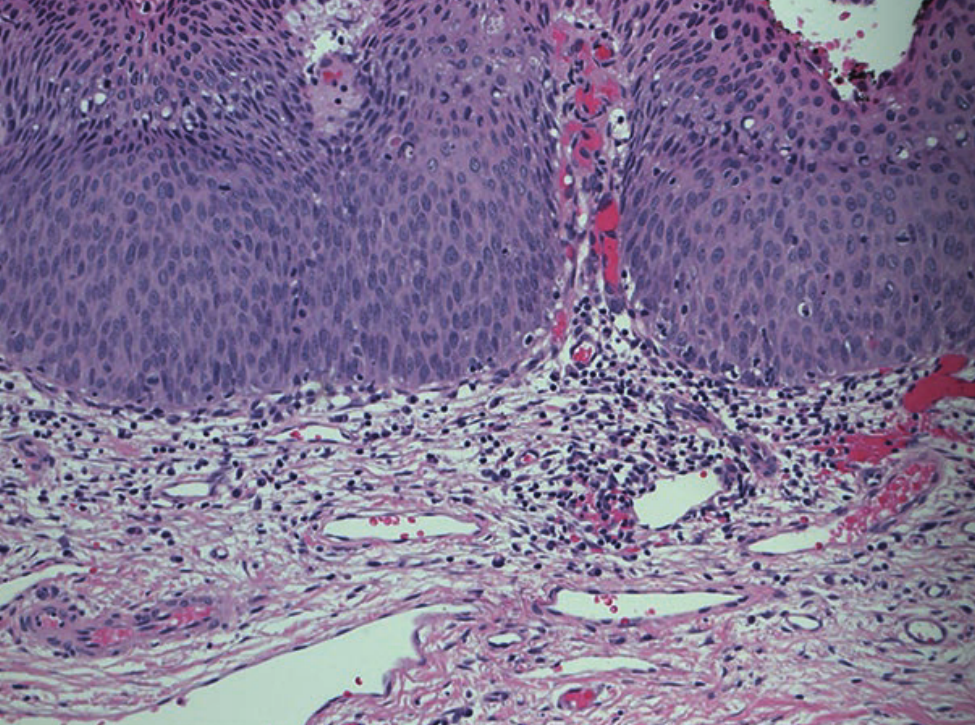

宫颈癌和HGSIL/CIN2/CIN3的发展都与HPV基因组整合到宿主基因组中以及随后两个HPV早期基因产物E6和E7的表达有关,这两个基因产物分别使p53和pRb失活。病毒整合位点虽然随机分布在人类基因组内,但主要发生在人类DNA容易断裂的位点(例如,脆弱位点),并且似乎只影响HPV基因组本身的表达。具体地说,E1和E2在整合过程中最常被破坏,而E6和E7病毒癌基因被保留,导致结构性表达。E6和E7的表达在功能上是启动和维持肿瘤转化所必需的。在形态学上,在细胞水平上,高度上皮内病变的特点是核浆比高。而在组织学上,高度恶性病变表现为全厚度,细胞不成熟,有丝分裂活跃(Fig. 15.4)。

Fig 15.4 放大20倍CIN-2/CIN3组织苏木精-伊红染色